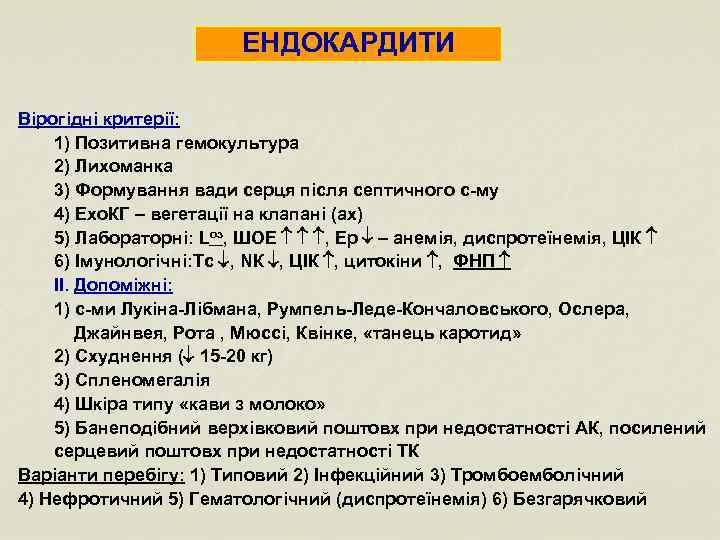

ЕНДОКАРДИТИ Вірогідні критерії: 1) Позитивна гемокультура 2) Лихоманка 3) Формування вади серця після септичного с-му 4) Ехо. КГ – вегетації на клапані (ах) 5) Лабораторні: Lоз, ШОЕ , Ер – анемія, диспротеїнемія, ЦІК 6) Імунологічні: Тс , NК , ЦІК , цитокіни , ФНП ІІ. Допоміжні: 1) с-ми Лукіна-Лібмана, Румпель-Леде-Кончаловського, Ослера, Джайнвея, Рота , Мюссі, Квінке, «танець каротид» 2) Схуднення ( 15 -20 кг) 3) Спленомегалія 4) Шкіра типу «кави з молоко» 5) Банеподібний верхівковий поштовх при недостатності АК, посилений серцевий поштовх при недостатності ТК Варіанти перебігу: 1) Типовий 2) Інфекційний 3) Тромбоемболічний 4) Нефротичний 5) Гематологічний (диспротеїнемія) 6) Безгарячковий